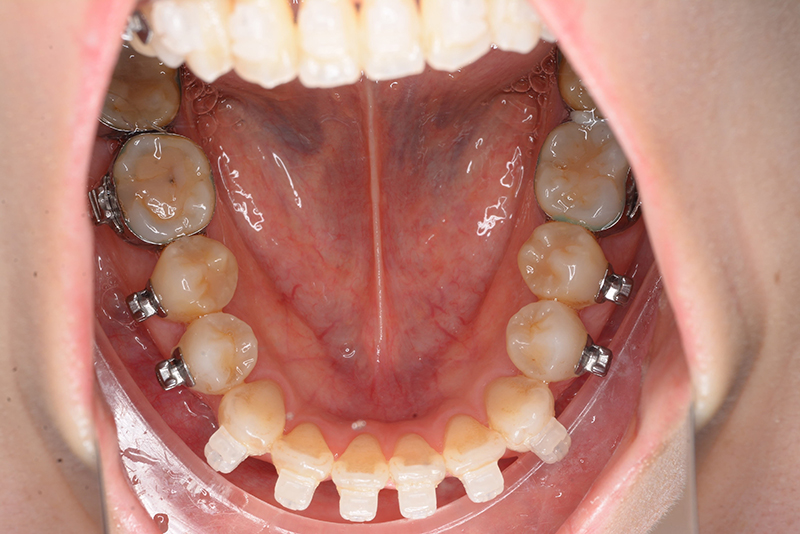

使用装置 0.018" × 0.025" standard edgewise

口腔内ゴムの使用 Class 5ヵ月、Up&Down 6ヵ月

口腔内所見 over jet 4.0mm、over bite 2.0mm、臼歯関係Ⅰ級、犬歯関係Ⅱ級で上顎前歯は唇側傾斜を呈しており、上下顎前突の様相を呈していた。